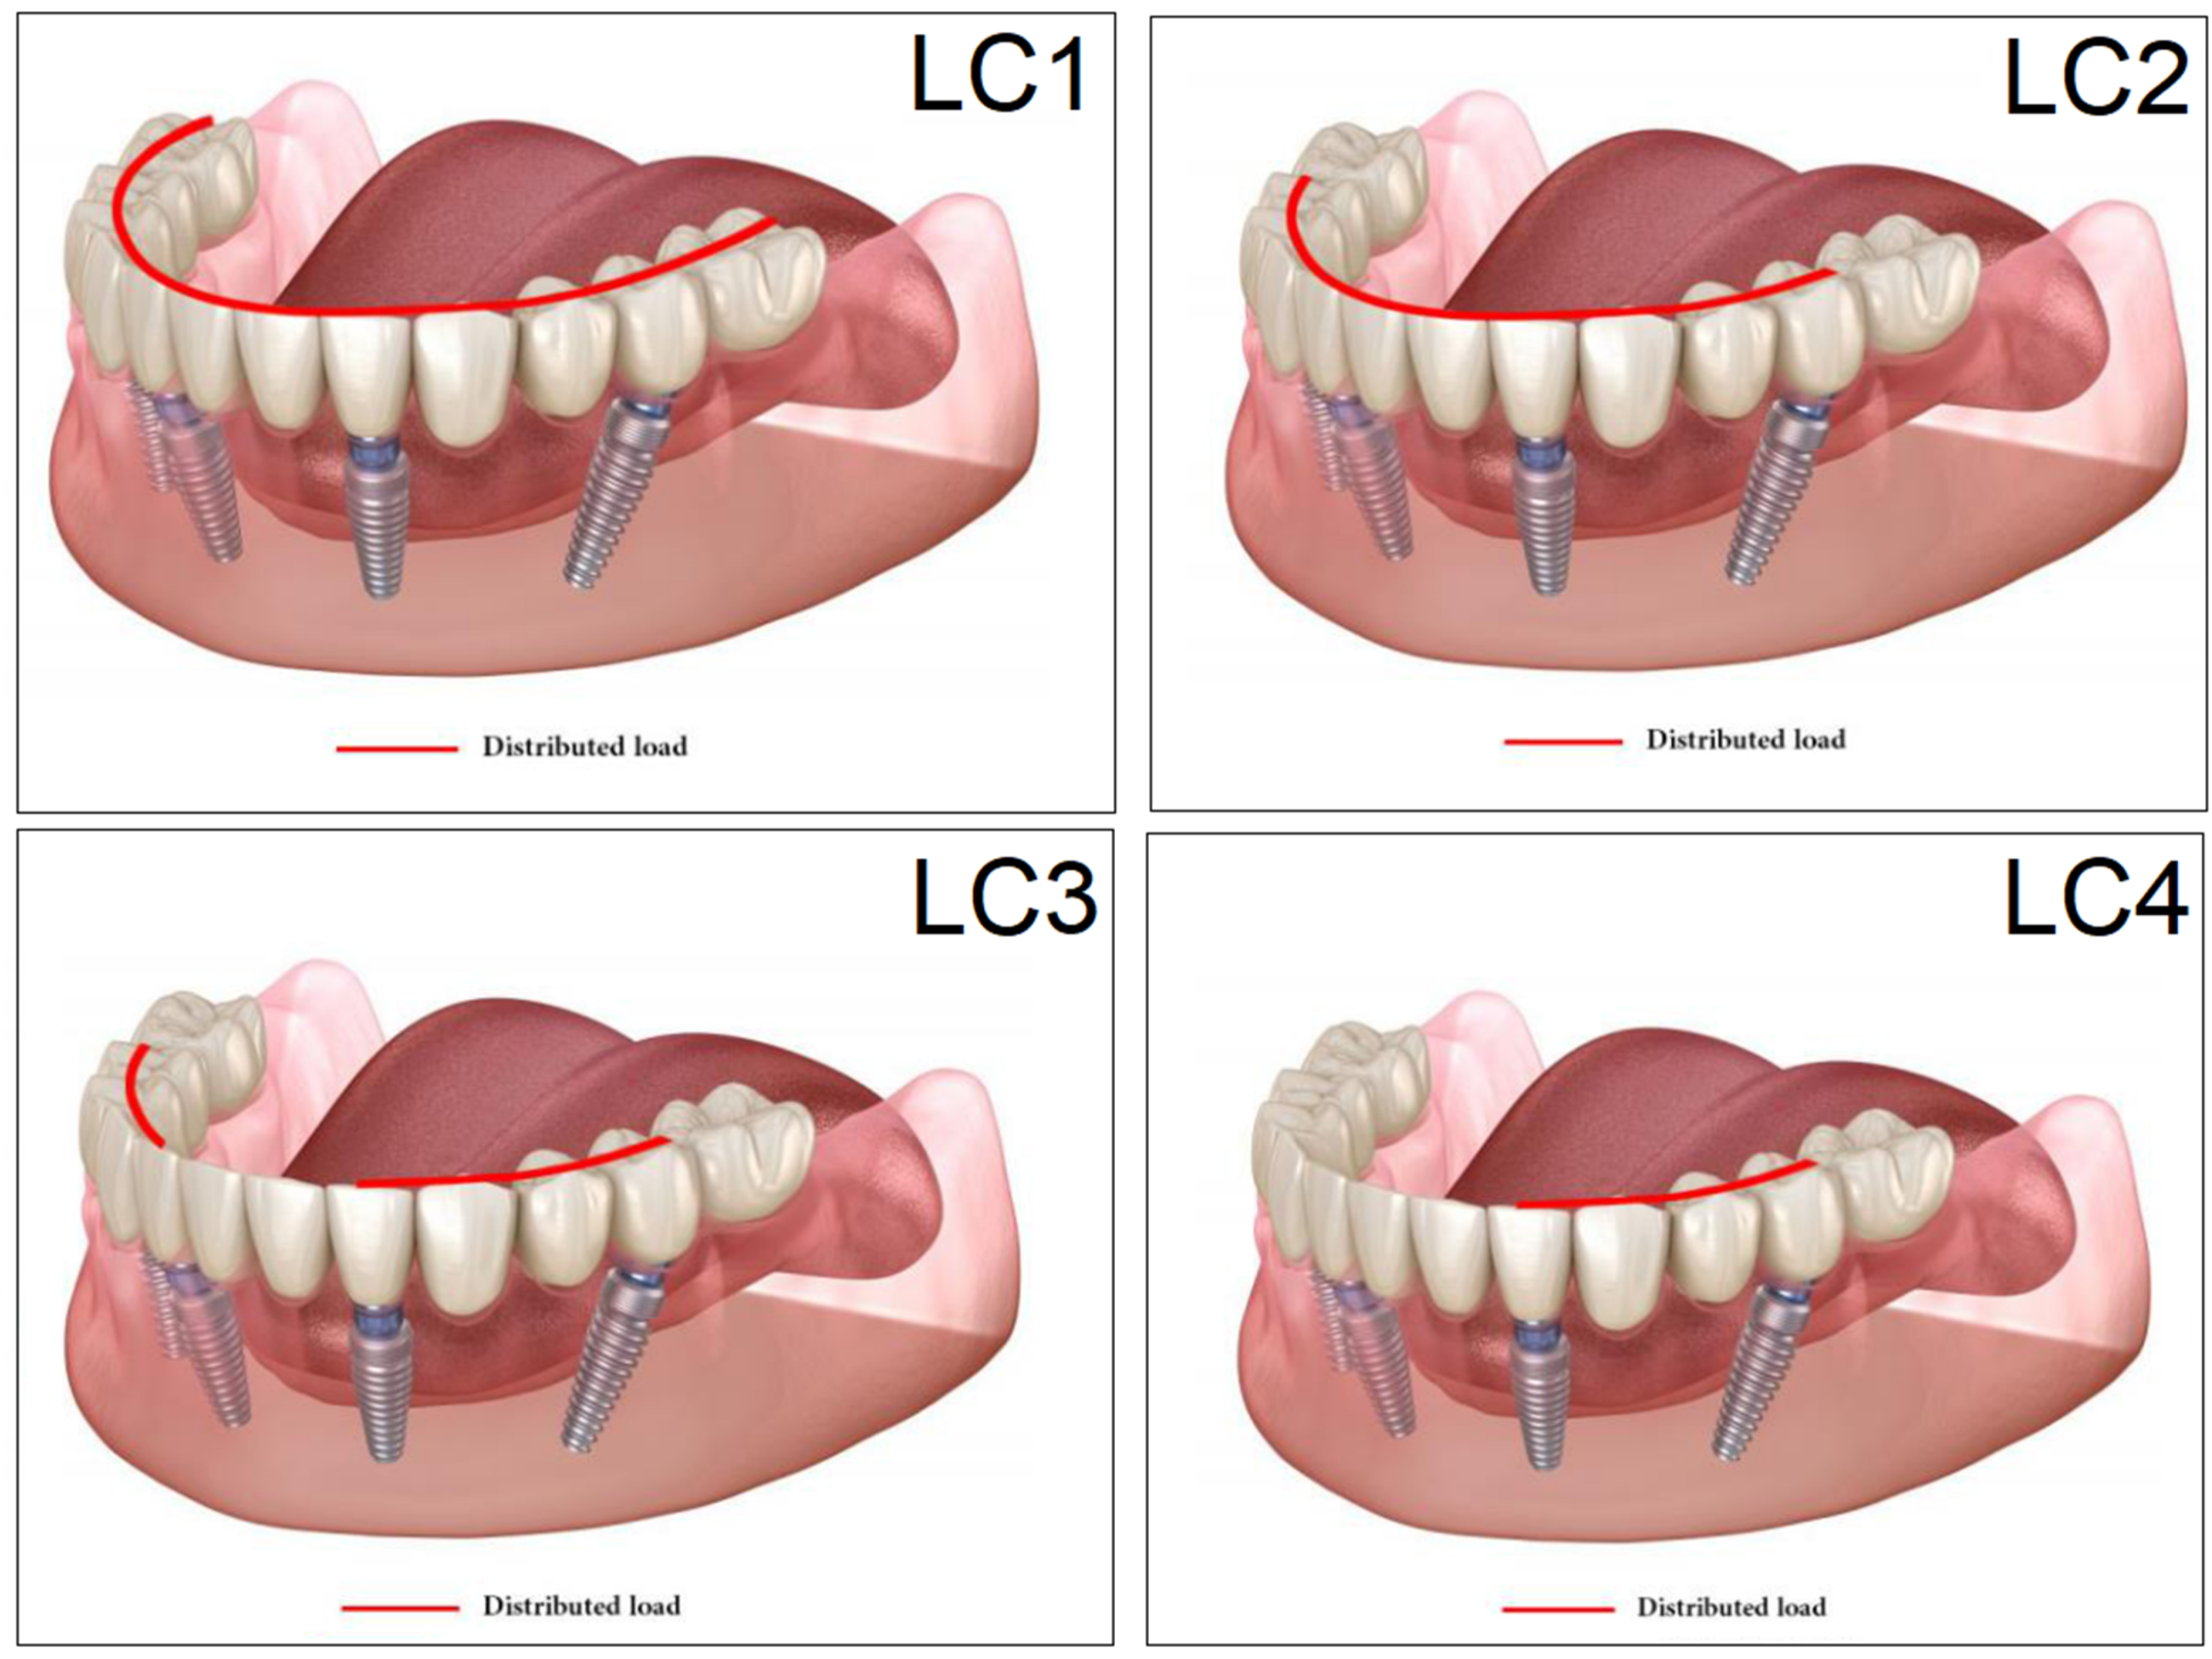

2.6. Loading, Occlusal Cases